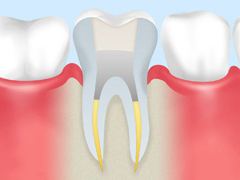

④:薬剤の充填

薬剤を根管内部に充填して密封し、再び細菌が侵入して炎症を起こすのを防止します。

⑤:土台の作成

歯根部に被せ物の土台を入れます。

⑥:被せ物の装着

マイクロスコープを使うことで、被せ物を装着する際、歯と被せ物の隙間をなくして適合性が高まります。

これにより、細菌が侵入して虫歯が再発するリスクを低減するほか、見た目も美しい仕上がりになります。